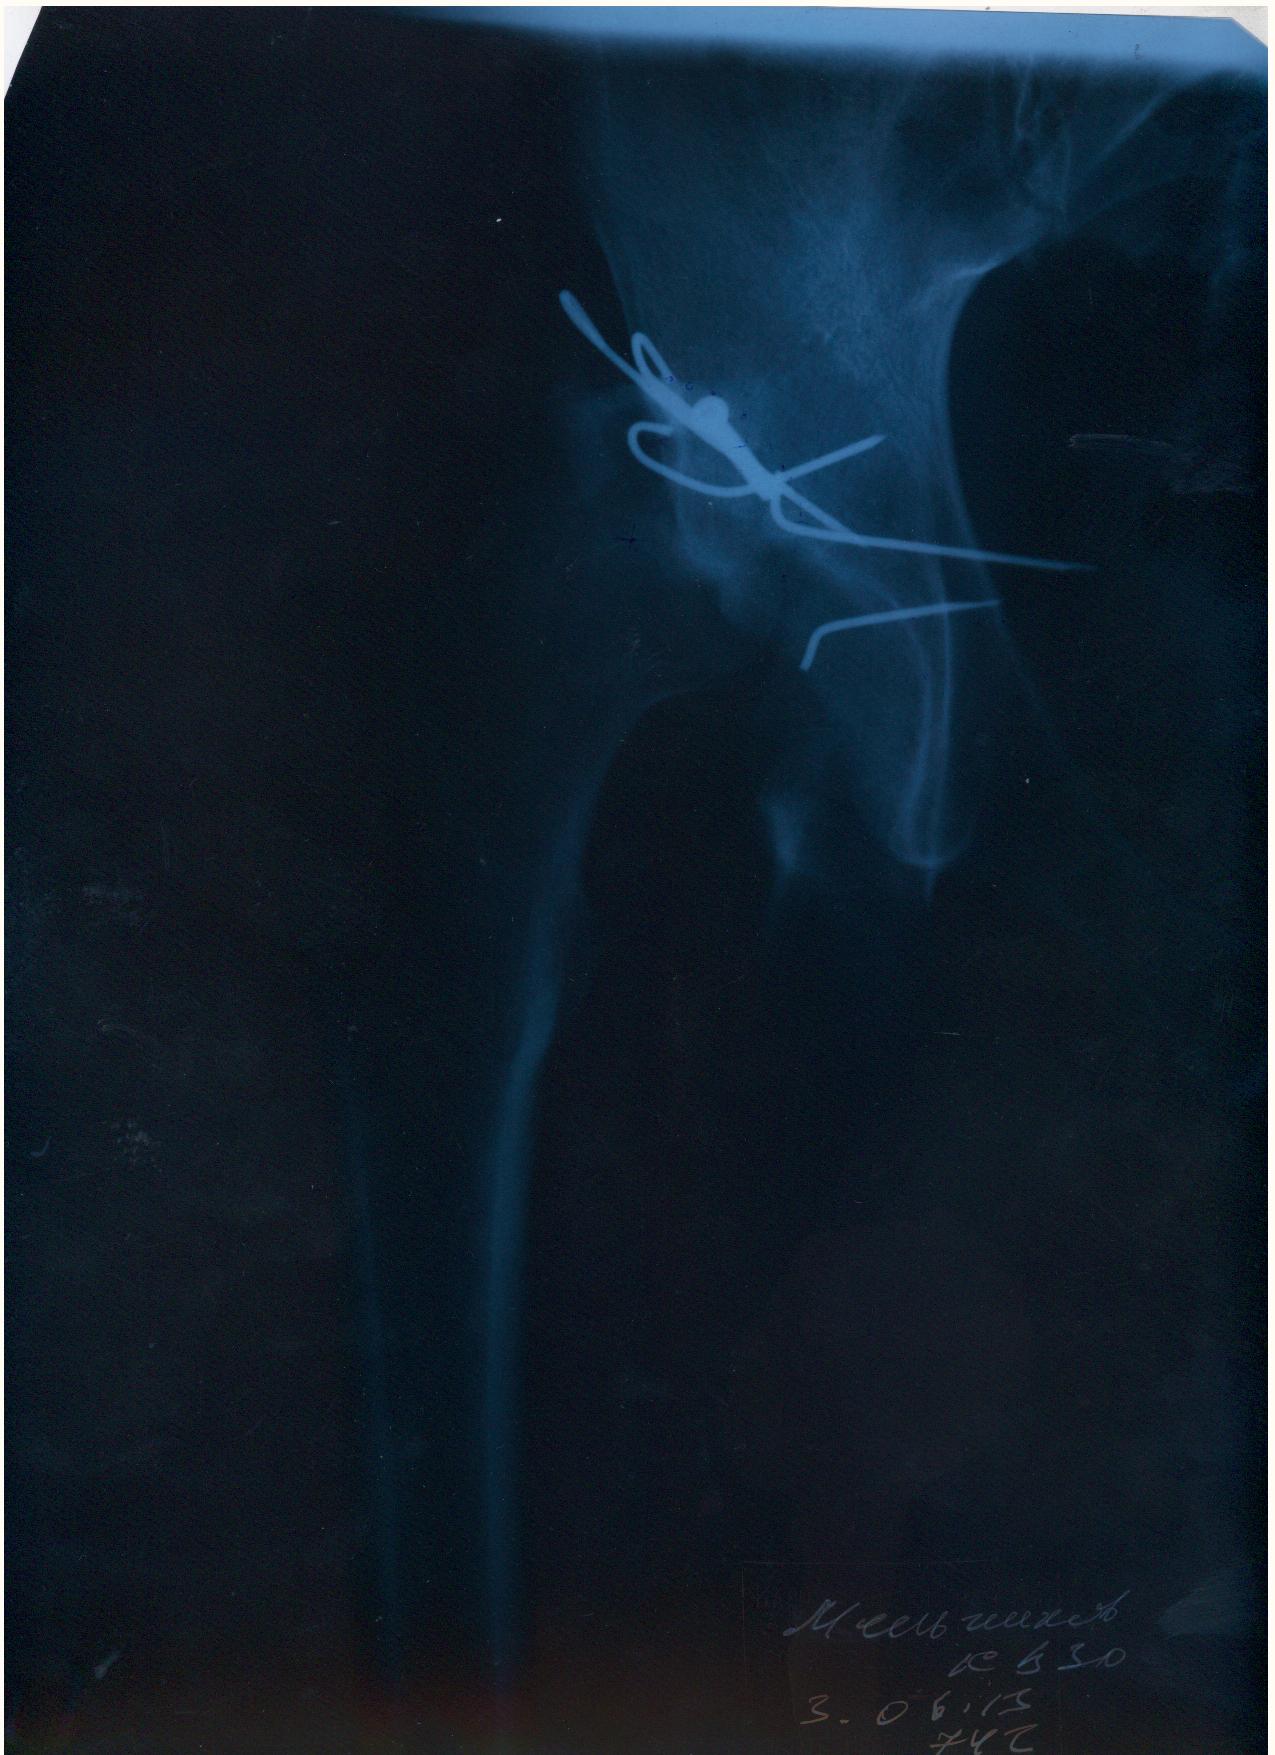

Мой товарищ попал в страшную аварию, виновник аварии как и два его пассажира погибли. Товарищ с пассажиром живы, но другу нужна сложная операция. Мы не можем никак найти врача способного прооперировать бедренный сустав, в пироговке отказали. Парню всего 30 лет всеми силами пытаемся поставить на ноги. выкладываю выписки и документы, могу выслать архивом на почту или привезти куда скажите.